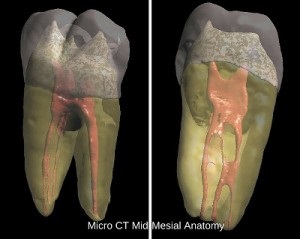

Azim et al, in a February 2015 JOE article wrote about the incidence of mid-mesial canals in lower molars. The authors found that in the 91 molars evaluated, 6 (6.6%) teeth had mid-mesial canals that could be located without troughing of the axis defined by the orifices of the MB and ML canals. Following troughing, a further 36 (39.6%) mid-mesial canals were found with 60% occurring in the second molars. Of the 42 mid-mesial canals found, 4 (9.5%) had a separate coronal and apical orifice, i.e. were a completely separate canal. In the remaining teeth, the mid-mesial canals joined either the MB or ML canal prior to the apical terminus.

This patient’s symptoms resolved within days and she has been asymptomatic since. My expectation is that we will see a significant reduction in the size of the lesion at our one year recall. Most dental office may treat 10-15 lower molars in an average year. One could expect then to find one mid-mesial canal every couple of years. While enhanced optics and 3D imaging surely helps with the discovery process, the dentist must be vigilant to be on the lookout for these black sheep canals.